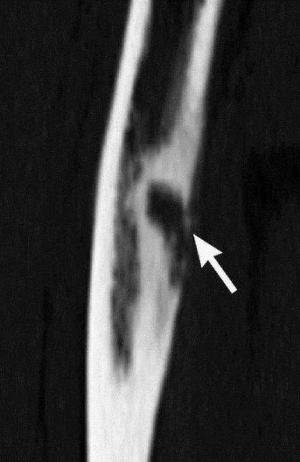

- Компьютерная томография и рентгенографические исследования кости бедра. Они позволят с высокой достоверностью подтвердить деструкцию костной структуры.